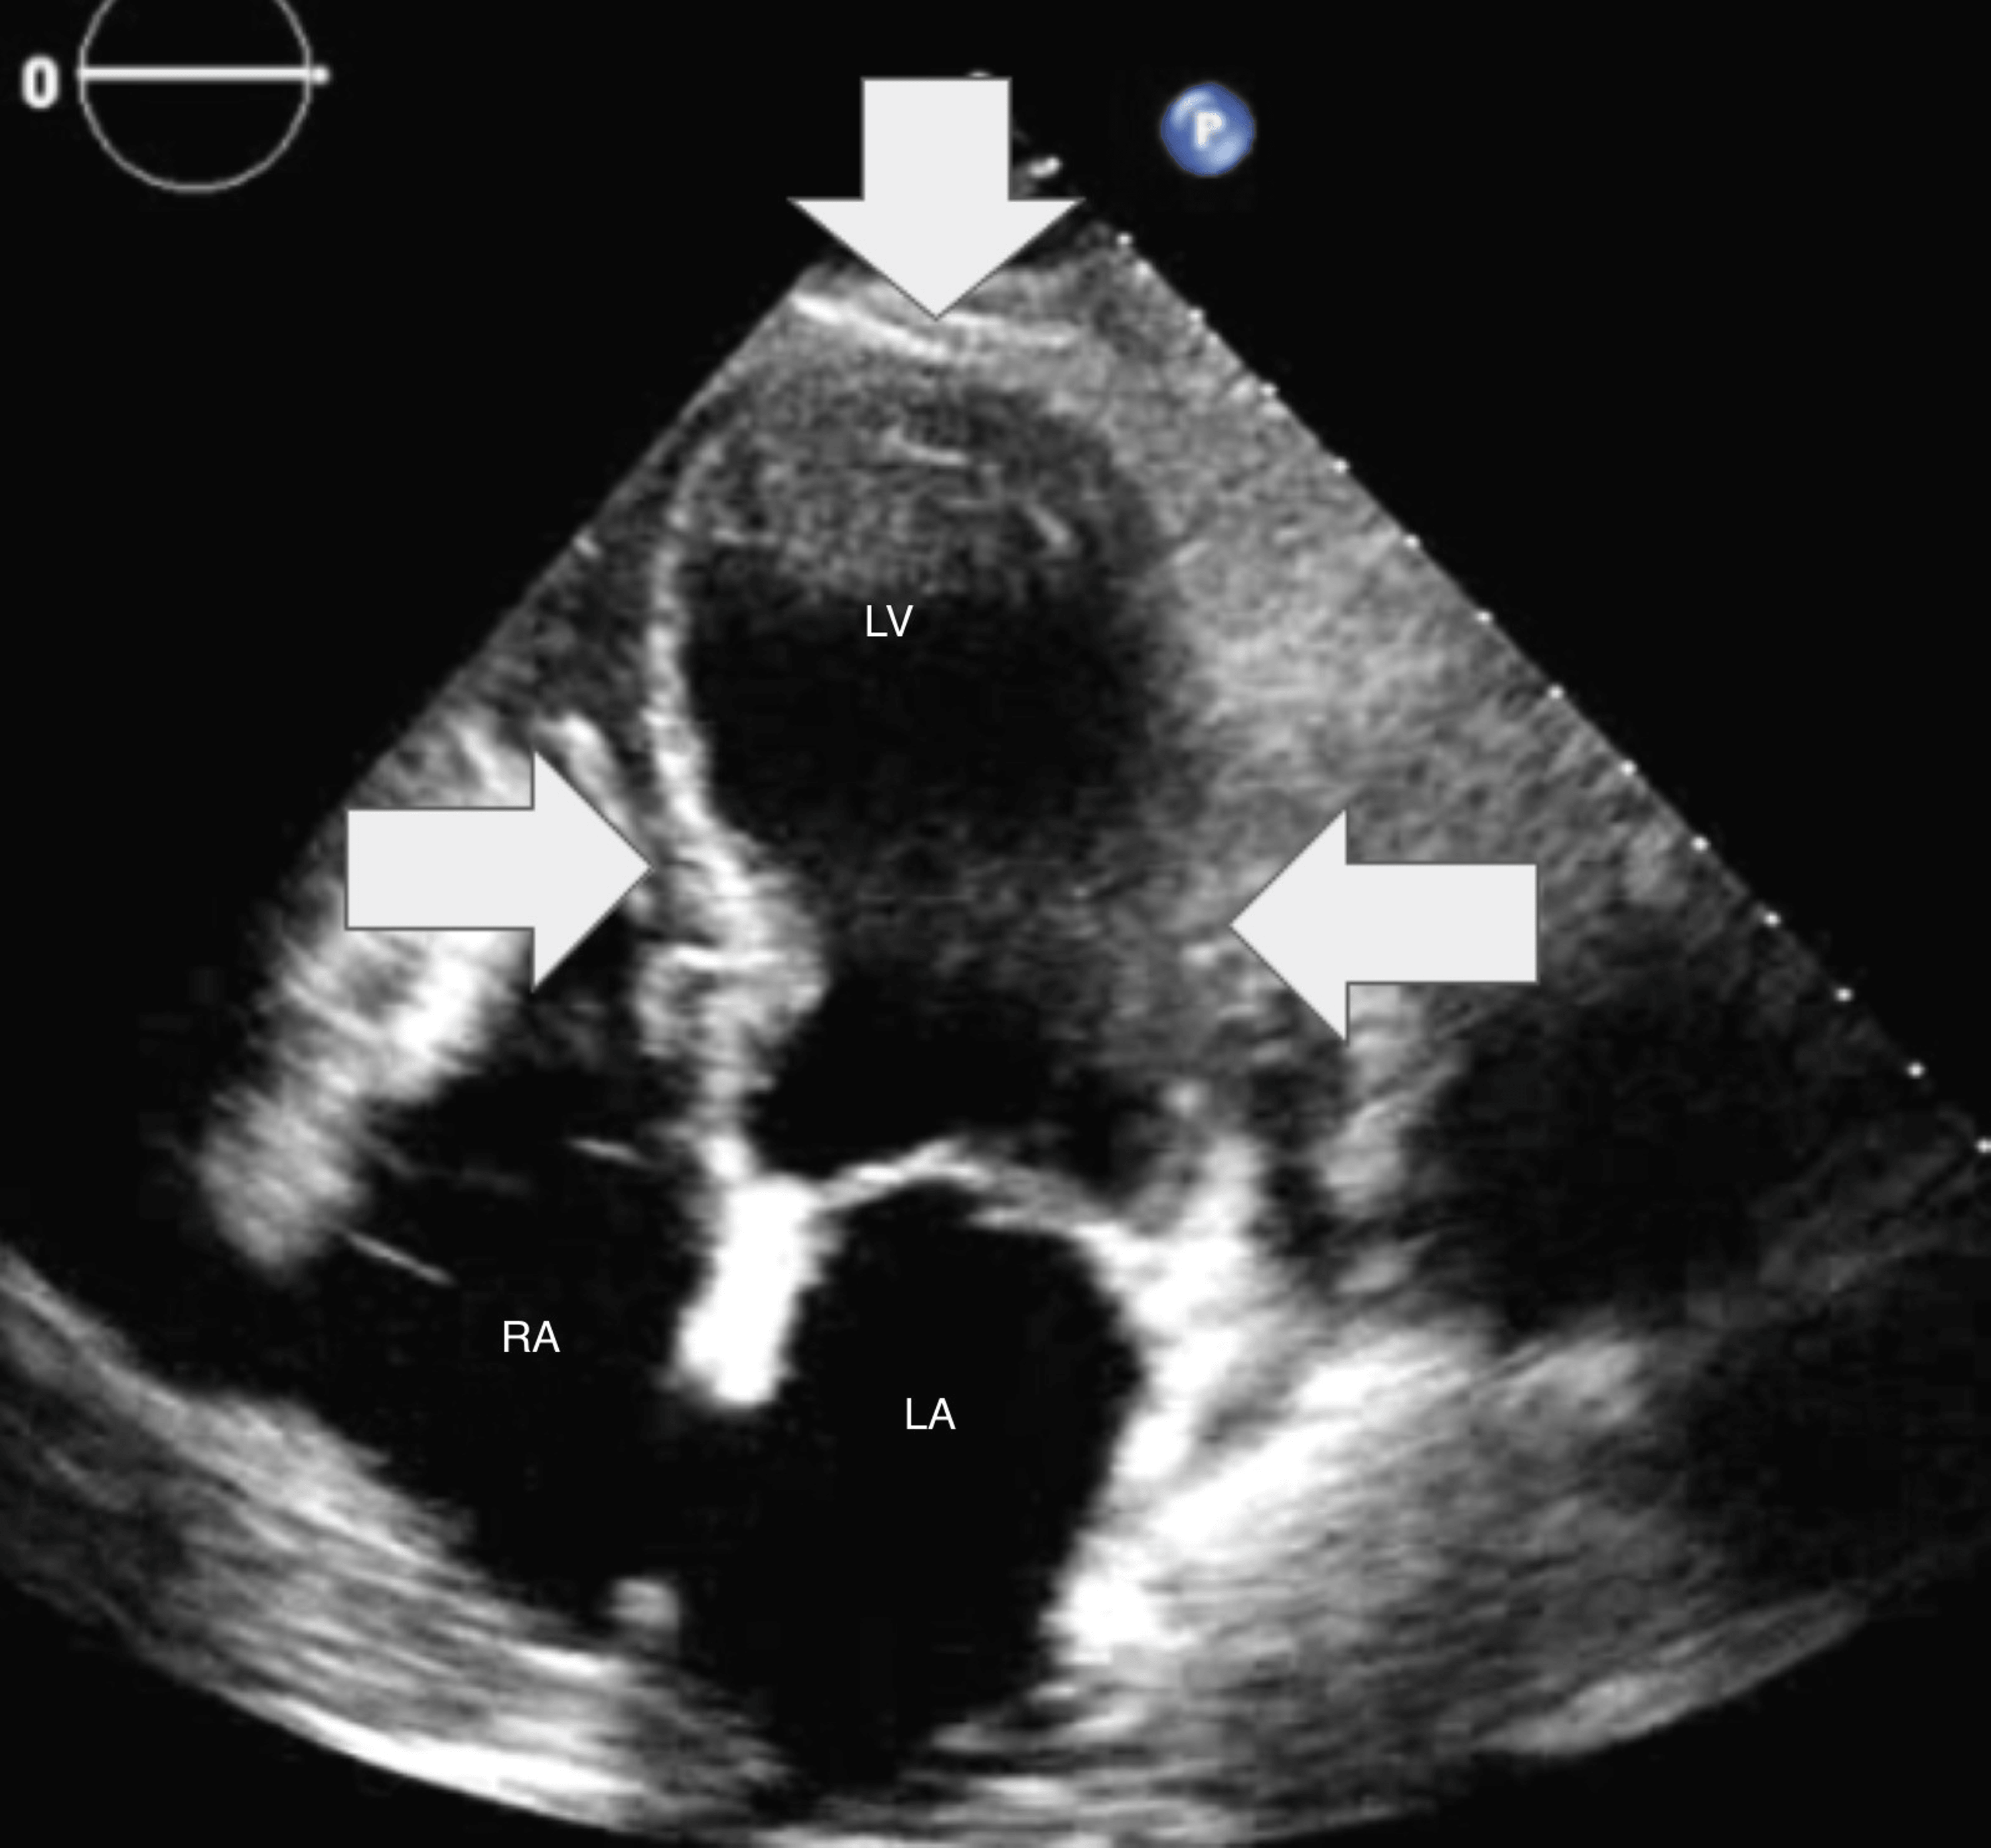

From www.researchgate.net

Transthoracic echocardiogram (fourchamber apical view in systole Apical Akinesis In most cases, thrombus is located. Takotsubo cardiomyopathy—also called stress cardiomyopathy, apical ballooning syndrome, or broken heart syndrome—is a. In a database analysis of patients with anterior wall stemi with apical akinesis or dyskinesis (on echocardiography performed. The apical ballooning syndrome is easily recognized due to its characteristic morphology and is associated with typical complications of apical akinesis (thrombus formation). Apical Akinesis.